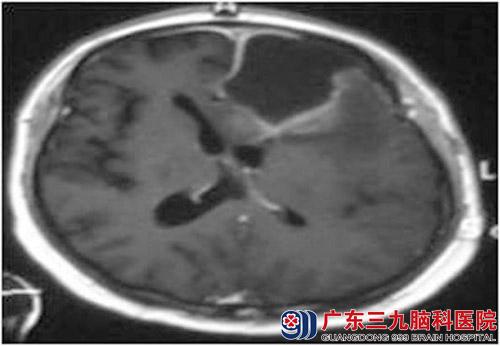

冯先生,48岁,于2009年7月因癫痫症状来广东三九脑科医院就诊,头部MR检查示左额叶占位,全麻下行左额叶占位切除术,术后病理示(左额叶)肥胖型星行细胞瘤,WHOII;局部为间变性星行细胞瘤,WHOIII级。术后尼莫司汀同步放化疗疗,适形调强放疗完成5400cgy,后继续行四程辅助化疗。治疗后恢复良好。2010年3月3日复查头颅MR示现术腔旁异常强化影及周围水肿范围较前明显增大。不能排除肿瘤复发。遂更换替莫唑胺化疗8程。后定期随访复查,颅内无肿瘤复发。目前治疗后5年,冯先生在2014年8月复查头颅MR未见明确肿瘤复发征象,目前患者精神良好,记忆力、计算力均无明显变差,无不适主诉。建议每年复查。